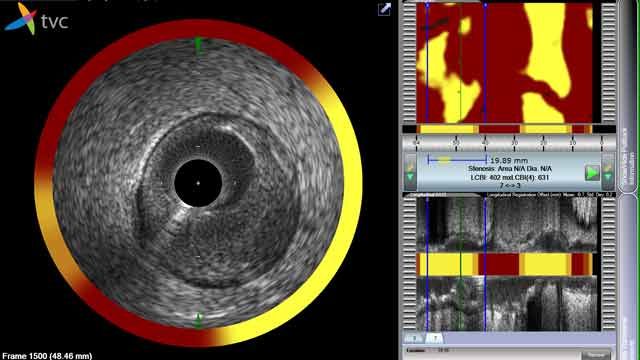

The TVC Imaging System user interface, with visualization tools for transverse IVUS, chemogram, and longitudinal IVUS.

A patient with lipid core plaques (LCP) is more vulnerable to coronary artery disease (CAD), the number one killer in developed countries such as the United States. To help cardiologists detect LCP, Infraredx developed the TVC Imaging System™. The TVC Imaging System is the only FDA-approved medical device for LCP detection. It combines near-infrared spectroscopy (NIRS) with intravascular ultrasound (IVUS) in a single coronary catheter to provide information about vessel composition and structure.